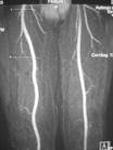

Ablavar is the first and only blood pool contrast agent approved for magnetic resonance angiography to evaluate aortoiliac occlusive disease (AIOD) in patients with known or suspected peripheral vascular disease. The albumin-binding properties of Ablavar make it designed for vascular imaging, allowing multiple images to be obtained using a single, low dose injection. Ablavar is clinically proven to produce high resolution MRA images, combining both dynamic (first pass) and steady state imaging, resulting in diagnostic accuracy comparable to conventional X-ray angiography, the current standard of care for diagnosing vascular disease such as AIOD.